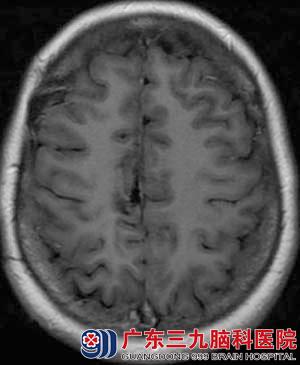

▲2015-4术后放化疗后5年余

2015年4月患者复查头颅MR示未出现复发征象,现治疗后5年余,已达临床治愈。